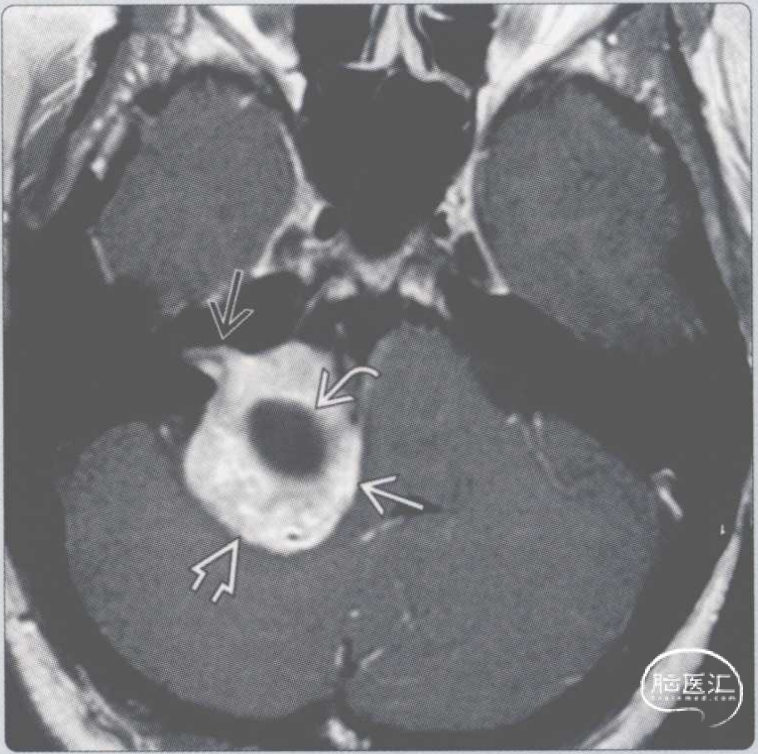

【影像时间·290】一位前庭神经鞘瘤患者